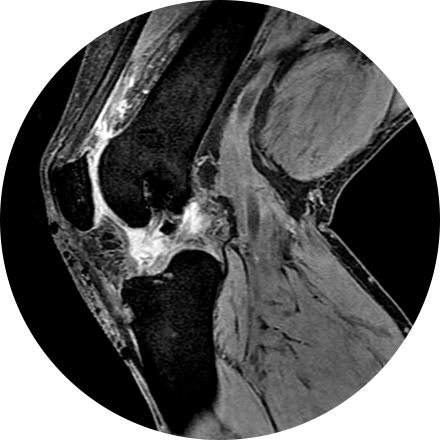

Arthrogram

An arthrogram is an X-ray exam of a joint, using a contrast agent and fluoroscopy (a live motion X-Ray). It is used to diagnose the cause of pain or restricted motion of a joint as well as injury to the components of the joint including, the tendons, soft tissues, ligaments, labrum, cartilage and bones. Often this procedure is used to image the shoulder and hip joints, and it is also used when investigating the knees, elbows, ankles and wrists. CT and MRI may also be used to gain additional images of the joint.